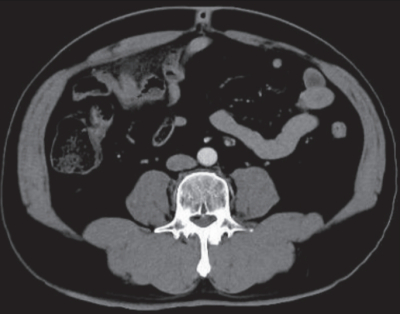

血液所見:赤血球 486 万、Hb 15.0 g/dL、Ht 44 %、白血球 18,000(好中球82 %、好酸球 1 %、好塩基球 1 %、単球 6 %、リンパ球 10 %)、血小板 26 万、PTINR 0.9(基準 0.9~1.1)。 血液生化学所見: 総蛋白 8.1 g/dL、 アルブミン5.1 g/dL、総ビリルビン 1.2 mg/dL、AST 23 U/L、ALT 30 U/L、LD 166 U/L(基準 120~245)、ALP 39 U/L(基準 38~113)、γ-GT 25 U/L(基準 8 ~50)、アミラーゼ 44 U/L(基準 37~160)、CK 64 U/L(基準 30~140)、尿素窒素 17 mg/dL、クレアチニン 1.2mg/dL、 尿酸 6.4 mg/dL、 血糖 109 mg/dL、Na 140 mEq/L、K 3.9 mEq/L、Cl 101 mEq/L、Ca 9.8 mg/dL。CRP 19 mg/dL。 腹部造影 CTを別に示す。

この患者の治療法で適切なのはどれか。

a. 緊急手術